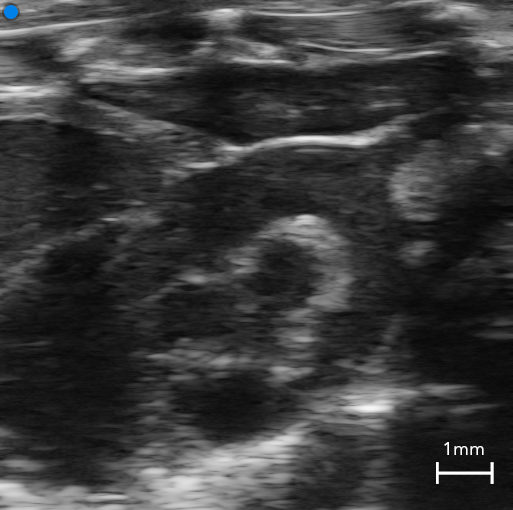

Measuring the velocity of blood flow is crucial to understanding disease states. Pulsed wave (PW) Doppler uses the Doppler principle that moving objects change the characteristic of sound waves. By sending short and quick pulses of sound, it becomes possible to accurately measure the velocity of blood in a precise location and in real time.

Using Color Doppler Mode, flow velocities within vessels are color-coded. The intensity of the color is a function of velocity. Flow towards and away from the transducer is indicated either as red or blue, respectively.

Color Doppler - Renal vein/artery